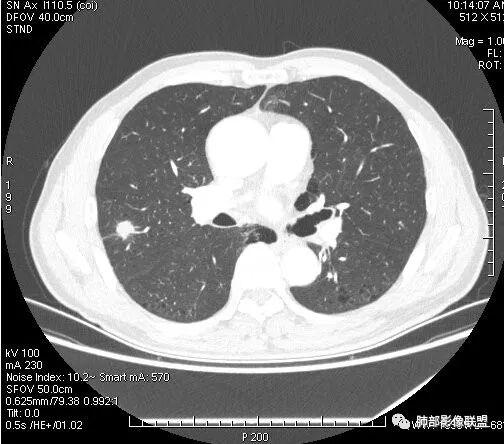

影像学改变:

1.右肺上叶后段类圆形结节影,密度不均,有坏死空洞,坏死比较彻底,内外壁都较清楚。

2.病灶有浅切迹,没有深分叶,毛刺大多细长且柔软。

3.可见棘状突起及胸膜牵拉,但未见胸膜凹陷。

什么意思?结节影有牵拉的动作,但似乎“出工不出力”,收缩力羸弱!

4.病灶轻到中度强化。病灶内血管走行较完好,病灶旁血管局部显示粗大。

5.支气管关系不确定。

6.灶周见小结节影(卫星灶),边界不甚清晰。

会是感染吗?

病灶相对局限,或偏安肺野一隅,小病灶带空洞,最常见的还是感染。

1.结核是常见的,坏死也够彻底,有卫星灶。疑问在于血管为什么不受累?

2.其他的慢性炎症。边界清楚符合慢性。慢性肺脓肿、隐球菌感染、奴卡菌感染等等都可以。可惜缺乏病原学依据。